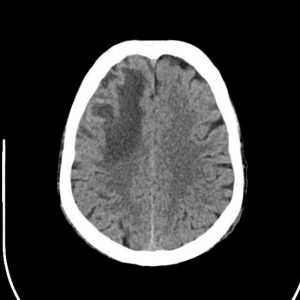

Xuất huyết não